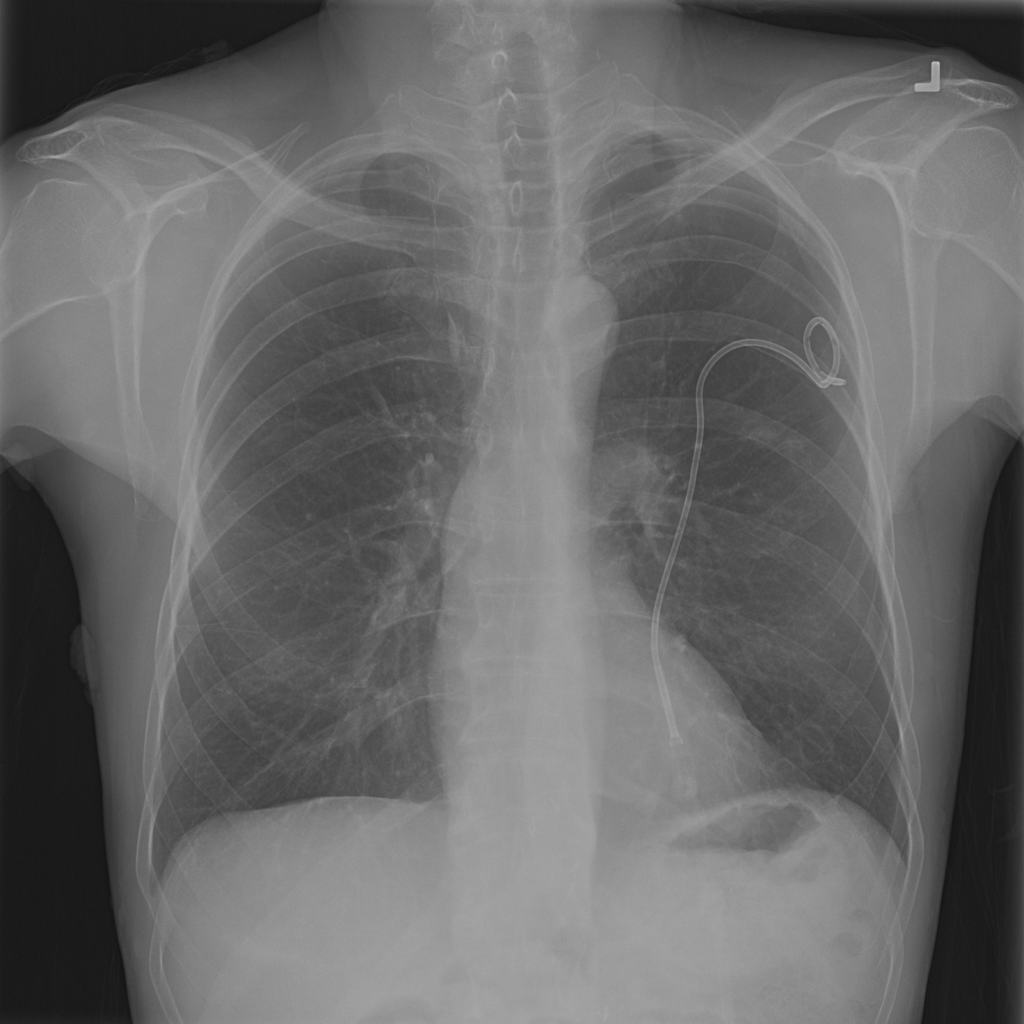

PAT-4639 · IMG-011Pneumothorax

PAT-4639 · IMG-011

AP